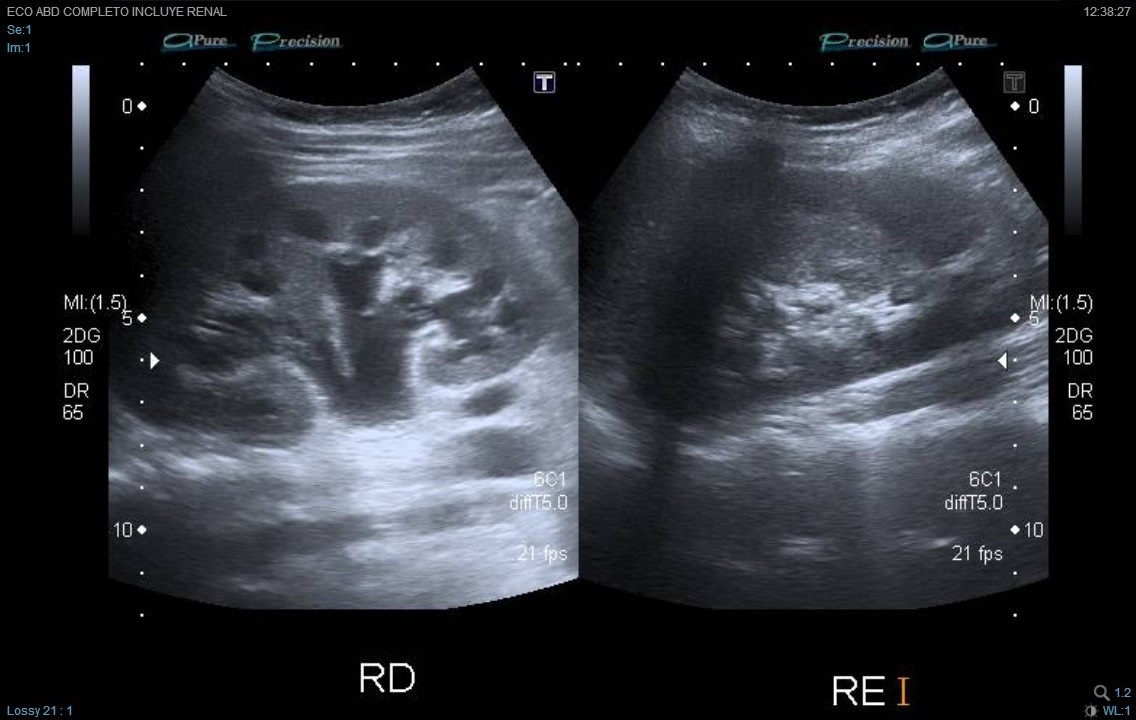

Ante los vómitos y la exploración abdominal se solicitaron: sedimento de orina pH 5, densidad 1030, hematíes 150/µl, proteínas 75 mg/dl, uratos amorfos; hemograma normal; química (función renal, proteínas totales, albúmina, electrolitos incluyendo Na, K, Cl, Ca, Mg, fósforo) normal; urinocultivo negativo; coprocultivo y virus en heces negativo; radiografía de abdomen normal, no se visualiza imagen de litiasis; ecografía abdominal (Figs. 1 y 2): cálculo de 7-8 mm, casi en el meato ureteral derecho, a 5-6 mm de la vejiga, con moderada ureterohidronefrosis proximal. No había líquido libre intraperitoneal. No se observa apéndice engrosado. El riñón y la vía excretora urinaria izquierdos no mostraban alteraciones.

La ecografía ha supuesto un gran avance en el diagnóstico de los cálculos, especialmente en niños, en los que suelen ser de pequeño tamaño. El aspecto típico es el de una imagen hiperecogénica con sombra sónica posterior.